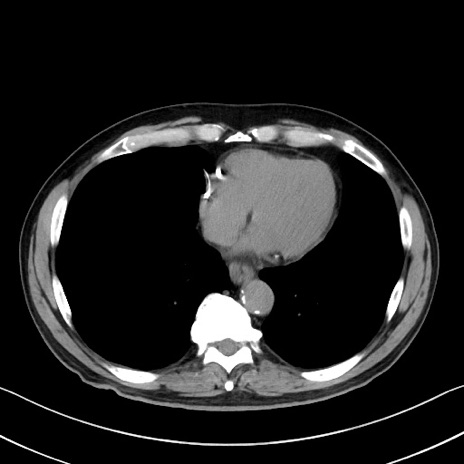

症例35(横断像)

【症例】70歳代 男性

【主訴】腹部膨満、嘔吐

【現病歴】昨日より腹部膨満感出現。本日増悪し、仙痛出現。嘔吐あり、受診。

【既往歴】糖尿病、胆摘後

【身体所見】BP 149/80mmHg、HR 74/min、BT 35.9℃、腹部:膨満、軟、圧痛なし。腸雑音減弱あり。上腹部正中切開瘢痕あり。

【データ】WBC 13500、CRP 1.72